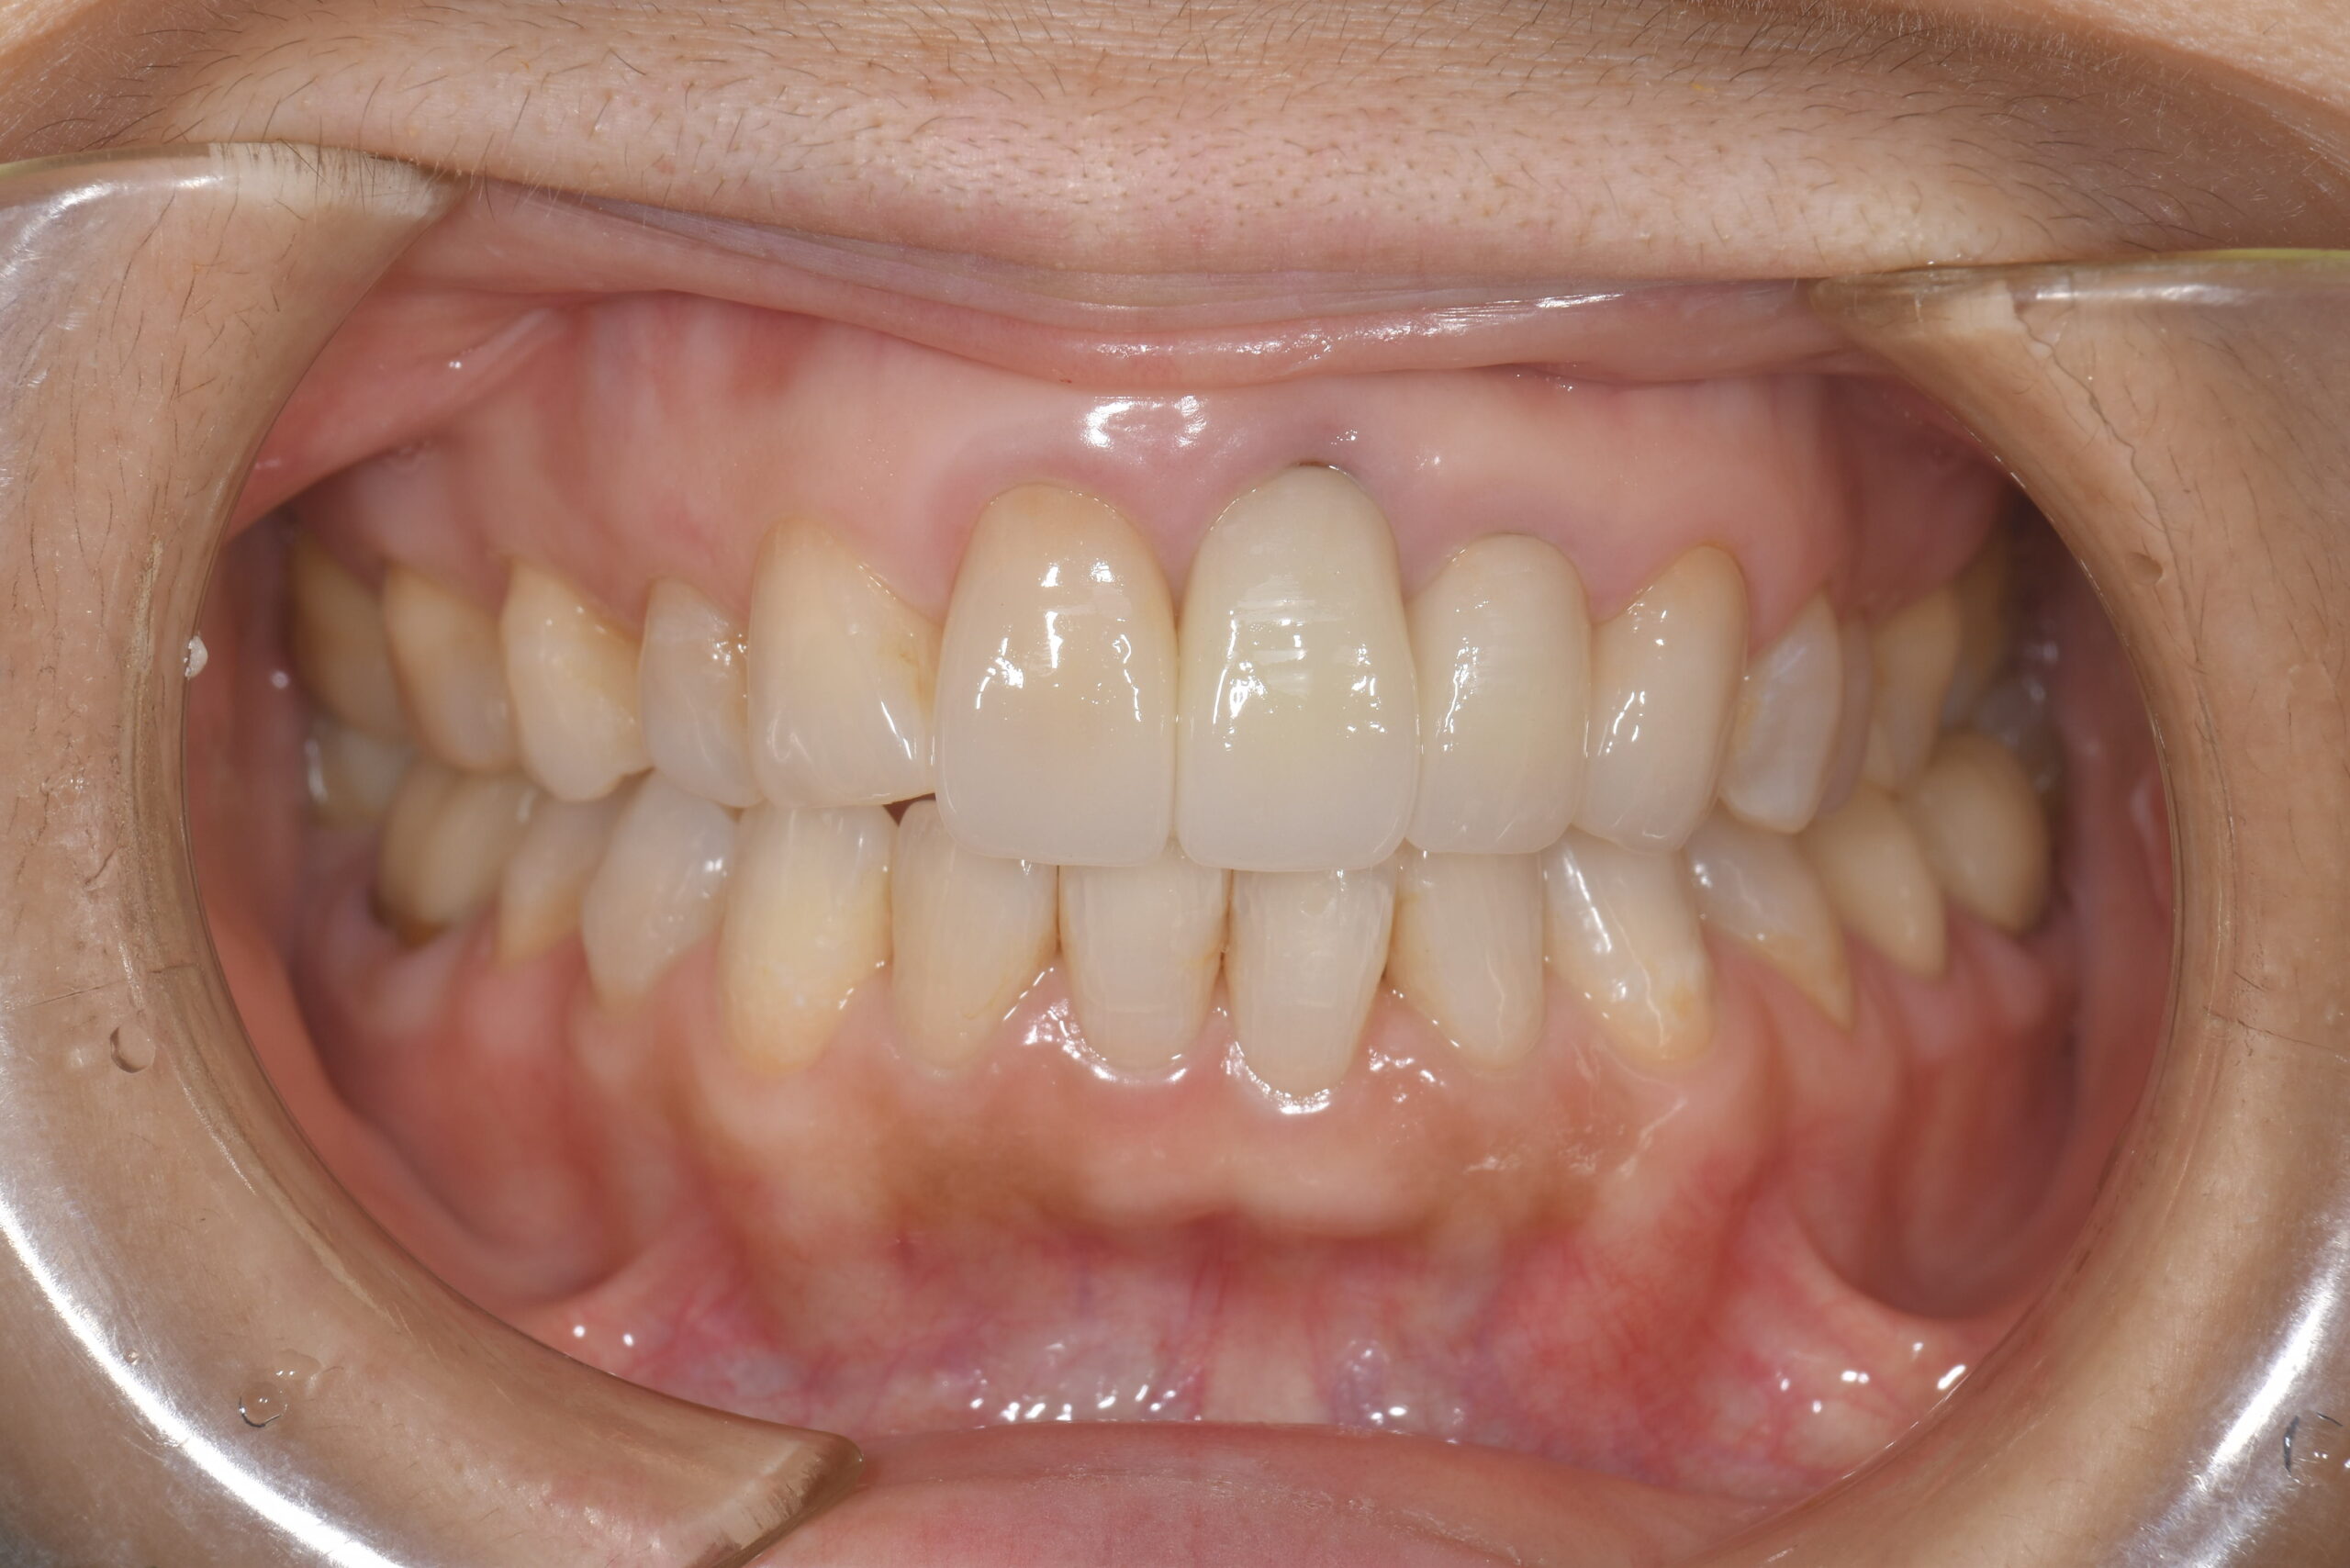

After -正面-

| 施術内容 | 金属アレルギー予防を目的に、金属フリーの自費補綴へ変更。適合性・清掃性・審美性の向上が得られています。 |

|---|---|

| 治療期間 | 約4ヶ月 |

| 費用 | オールセラミッククラウン 264,000円 オールセラミックインレー ハイブリットインレー 275,000円 |

| リスク・副作用 | 治療にともない、歯の破折や歯質の削合、場合によっては抜歯が必要となることがあります。また、金属や補綴物を除去する際に、完全に除去できない場合もあります。 |